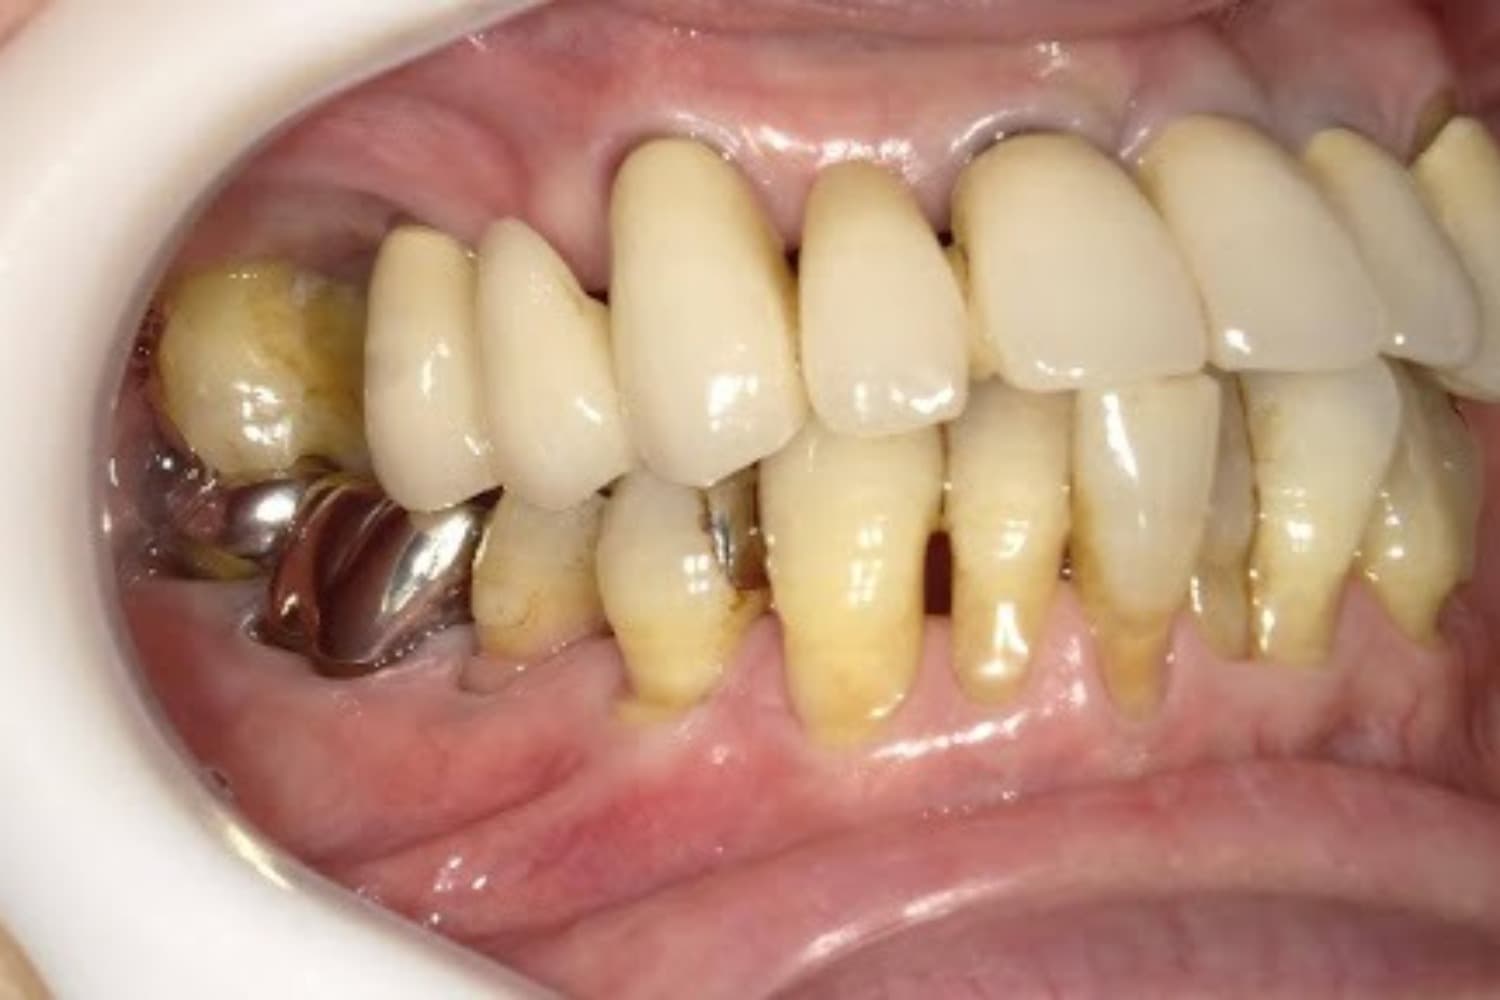

右上の歯のインプラント治療(50代女性)

Before

After

グラフトレスサイナスリフトをともなうインプラント治療

50代

女性

主訴

右上の歯が歯周病によって自然に抜け落ちてしまった

2ヵ月半

6回

363,000円(税込) 費用の内訳: 【インプラント基本料】330000円(税込み) 基本料金に以下を含む ・フィックスチャー及び手術費用 ・投薬費用、 ・レントゲン費用 ・インプラント上部費用(アバットメントおよびジルコニアクラウンの費用用) 【オプション費用】 ・グラフトレスサイナスリフト費用 33000円(税込み)

・手術後に痛み・腫れ・出血・合併症等を引き起こす恐れがあります。 ・噛む感覚がご自身の歯と異なることがあります。 ・見た目がご自身の歯と異なる場合があります。 ・手術後もメインテナンスを続けないと、インプラントが抜け落ちてしまう恐れがあります。